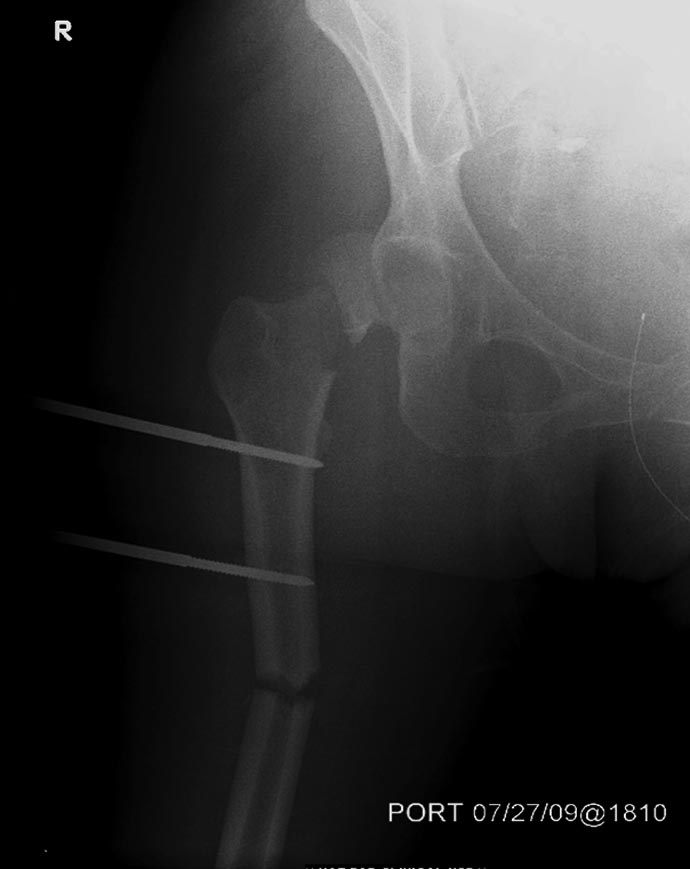

Здесь перечислены ортопедические повреждения: Rt. femoral shaft fracture, Rt femoral head fracture-dislocation, Rt distal femur fracture, Rt. open patella fracture, Rt. talus fracture dislocation, Rt. open humerus fracture, Left 5th metatarsal fracture, Left dislocation 1st TMT.

Интенсивные реанимационные мероприятия продолжаются в ICU, на следующий день сделана Irrigation &Debridement раны живота с последующим ушиванием серозной оболочки, наружный фиксатор на правое бедро. В связи со стабилизацией состояния получили добро на короткую операцию. Каккое из повреждении является более приоритетным? С чего начать?